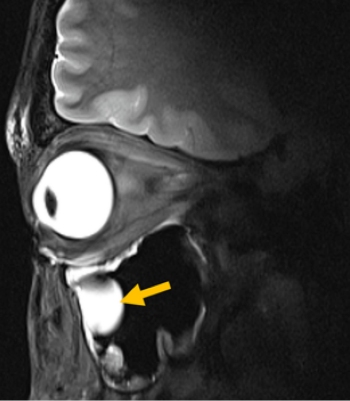

Bild: MRT-Bild eines Auges, der Augenhöhle und des Gehirns, Foto: © AG Niendorf, Max Delbrück Center

Entscheidend für die klinische Praxis ist zudem, dass die Antenne in bestehende MRT-Systeme passt, sodass keine neue Infrastruktur erforderlich wird. Validiert haben die Wissenschaftler*innen ihre Technologie anhand von MRT-Bildern des Auges, der Augenhöhle und des Gehirns bei einer Gruppe von Freiwilligen. Niendorf und sein Team arbeiteten dabei eng mit Forschenden des Universitätsklinikums Rostock zusammen und kombinierten so Expertise in MRT-Physik mit klinischer Ophthalmologie und translationaler Bildgebung.

Die Forschenden konnten zeigen, dass ihr System für den routinemäßigen klinischen Einsatz geeignet ist. „Wir sehen eine klare Relevanz für Anwendungen in der Augenheilkunde. Die neue Technologie ermöglicht anatomisch detaillierte MRT-Bilder des Auges mit hoher räumlicher Auflösung und Weichteilkontrast“, sagt Professor Oliver Stachs, Koautor der Publikation von der Universitätsmedizin Rostock. „Sie öffnet die Sicht auf (patho)physiologische Prozesse, die bislang weitgehend unzugänglich waren.“

Bild: MRT-Bild eines Auges, der Augenhöhle und des Gehirns, © AG Niendorf, Max Delbrück Center